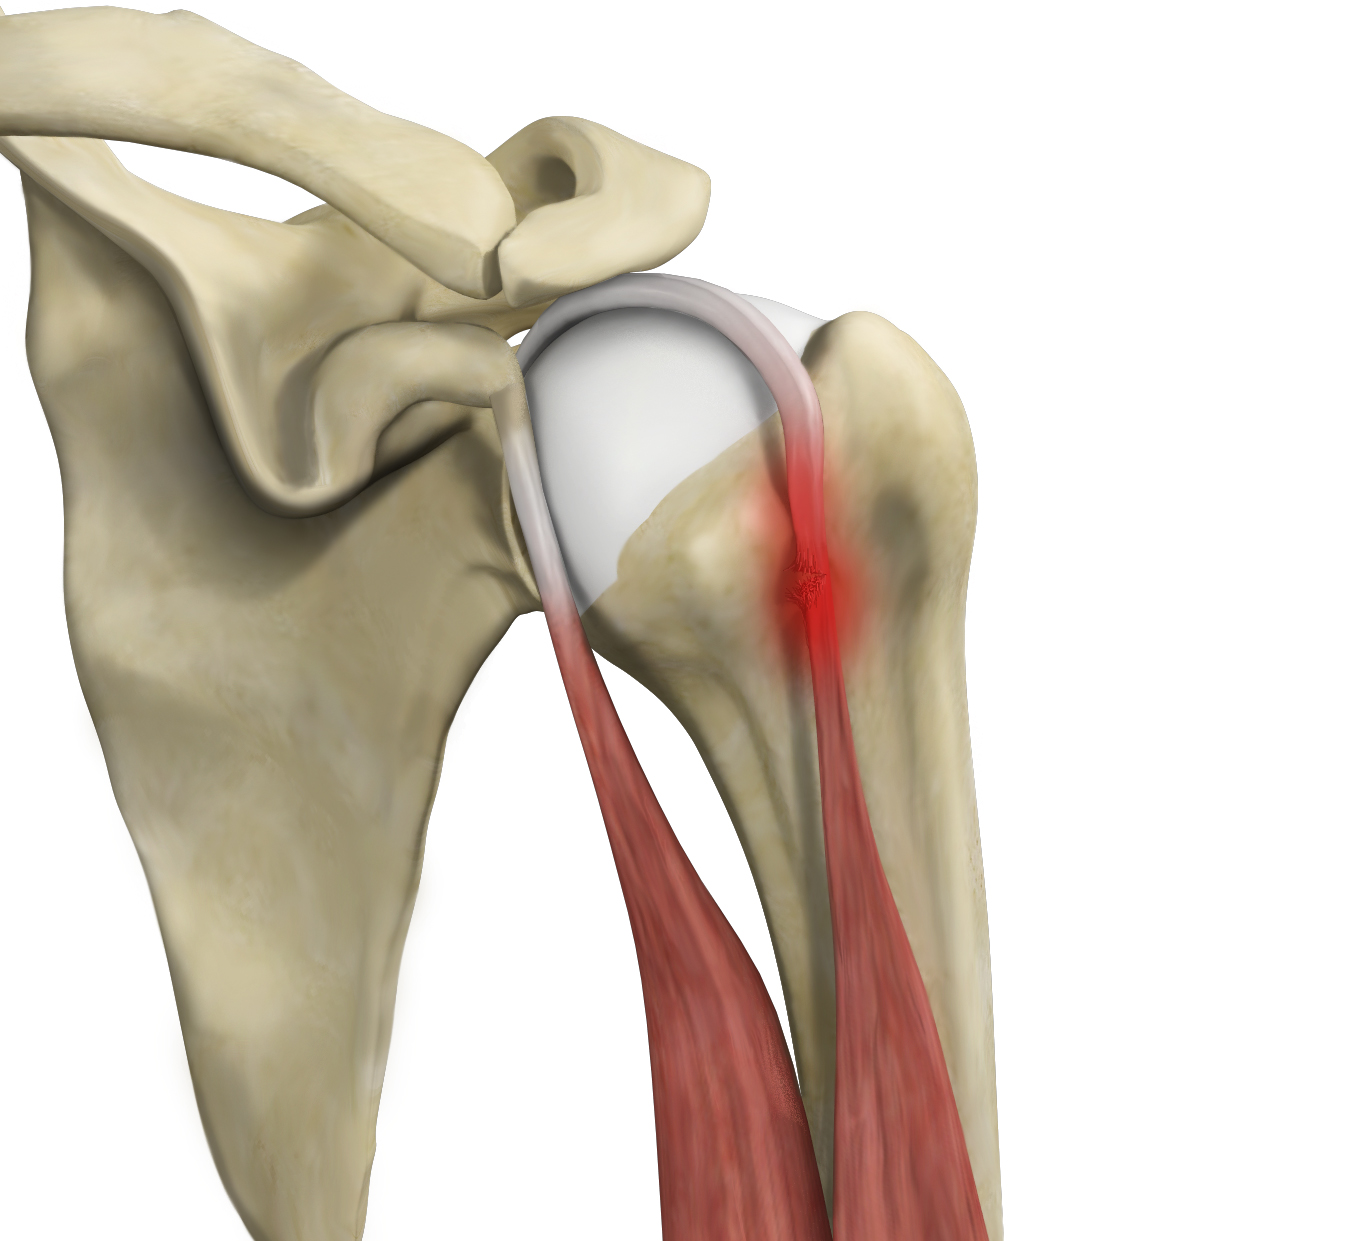

Rotator Cuff Tear

A rotator cuff tear is an injury where one or more of the tendons in the rotator cuff (the group of muscles and tendons that stabilize the shoulder and enable arm movement) become partially or completely torn.

Partial Rotator Cuff Tear

A partial rotator cuff tear is an incomplete tear that involves damage to a part of the tendon.